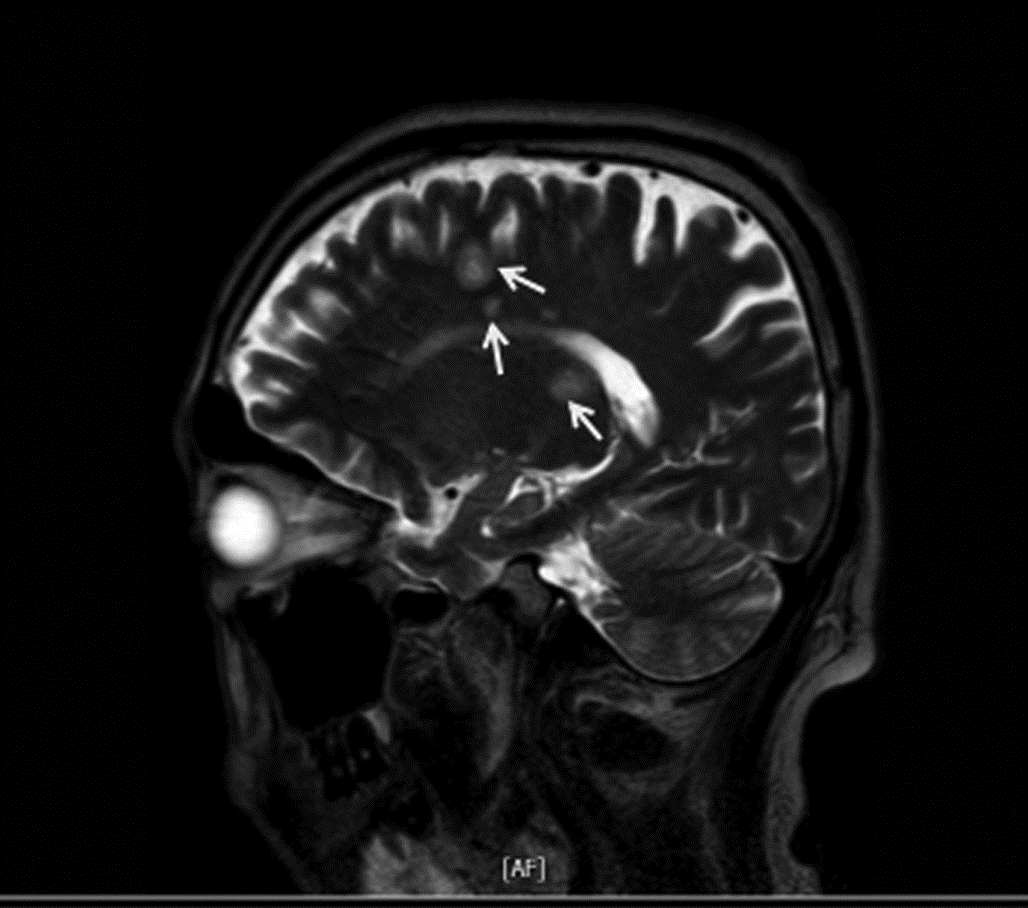

2型糖尿病合并肝脓肿继发脑脓肿1例报告

2022, 38(6): 1375-1376. DOI: 10.3969/j.issn.1001-5256.2022.06.031

摘要: